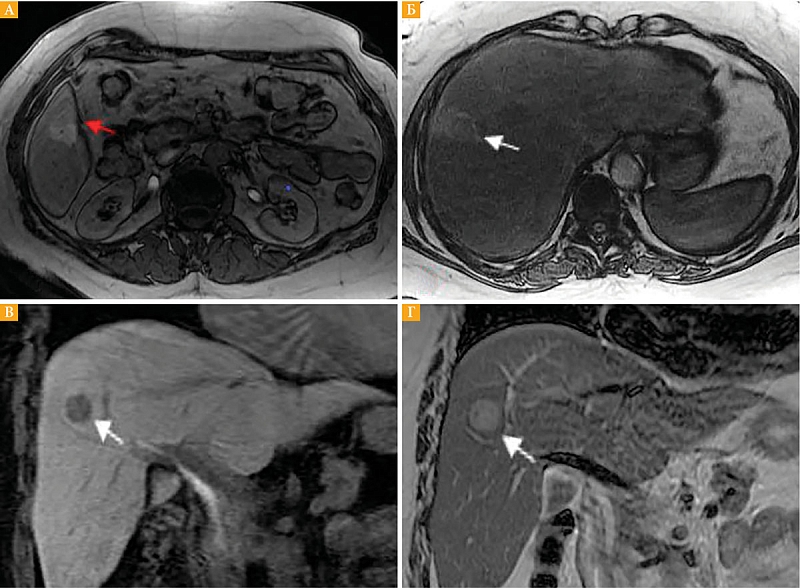

Рис. 3. Метастазы увеальной меланомы в печени: на диффузионно-взвешенных изображениях (DWI) с b-фактором 50  (А – сигнал от очагов гиперинтенсивный) и 1000 (Б – сигнал от очагов гиперинтенсивный)

На диффузионно-взвешенных изображениях (ДВИ) с использованием b-факторов b50, b1000 и картах измеряемого коэффициента диффузии (ADC, eADC) все метастазы характеризовались ограничением диффузии: гиперинтенсивный сигнал на DWI, гипоинтенсивный – на изображениях ADC и гиперинтенсивный – на изображениях eADC (рис. 3).

По данным M. Wagner и соавт., использование режима ДВИ незначительно повышает чувствительность обнаружения метастазов УМ в печени [26]. Однако в этой работе представлены изображения только с низким и средним значениями b-фактора. Показано, что низкие значения b-фактора чувствительны для выявления любых образований печени [27]. В нашем исследовании использовались ДВИ с низким, средним и высокими значениям b-фактора, в том числе 500 и 1000, которые более специфичны для обнаружения злокачественных новообразований печени. В целом использование разных значений b-факторов не только повышает выявляемость очаговых образований печени, но и позволяет определить их характеристики [28]. Особенно важна роль ДВИ при дифференциальной диагностике мелких очагов печени с атипичным накоплением контрастного препарата [29].